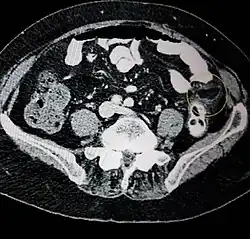

Ultrasound and CT scans are the normal means of positive diagnosis of epiploic appendagitis. Ultrasound scans show "an oval, non-compressible hyperechoic mass with a subtle hypoechoic rim directly under the site of maximum tenderness".[4] Normally, epiploic appendages cannot be seen on CT scan.[4] After cross-sectional imaging and the increased use of abdominal CT for evaluating lower abdominal pain, EA is increasingly diagnosed. Pathognomonic CT scan data represent EA as 2–4 cm, oval shaped, fat density lesions, surrounded by inflammation. Contrasting with diverticulitis findings, the colonic wall is mostly unchanged.